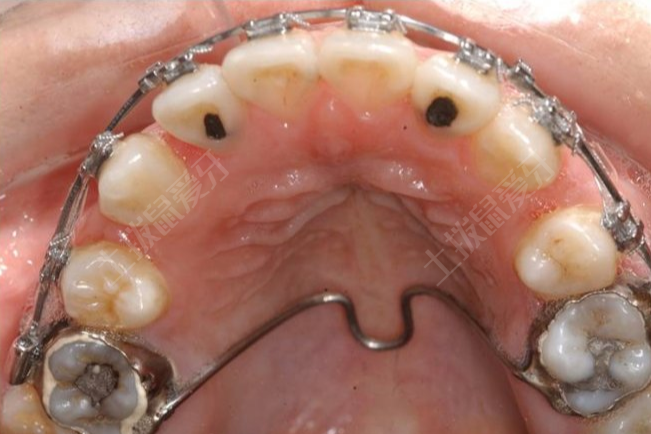

正畸牙列擁擠度,可以用牙弓應(yīng)有長(zhǎng)度減去牙弓現(xiàn)有長(zhǎng)度計(jì)算?;颊呖梢杂脠A規(guī)或游標(biāo)卡尺在模型上測(cè)量每個(gè)牙齒的最大寬度,其總和即為牙弓應(yīng)有寬度,也可以使用0.5mm的黃銅絲測(cè)量牙弓現(xiàn)有寬度,從后牙和前牙接觸點(diǎn)順著牙槽嵴頂,按照一定標(biāo)志點(diǎn)到另一側(cè)后牙與前牙的接觸點(diǎn),測(cè)量三次,取平均值計(jì)算即可,如果牙弓擁擠度小于4mm是輕度擁擠,可以考慮不拔牙。

如果測(cè)量牙齒擁擠的程度,則使用牙弓的適當(dāng)長(zhǎng)度和牙弓的現(xiàn)有長(zhǎng)度。這兩種長(zhǎng)度之間的差異稱為擁擠。如果擁擠程度相對(duì)較大,可以使用游標(biāo)卡尺或量規(guī)在牙齒模型上進(jìn)行測(cè)量。這種情況可以用一些牙齒矯正器來(lái)治療。戴牙套時(shí)應(yīng)該注意清潔牙齒。應(yīng)該記得每天早晚刷牙,飯后用清水漱口。避免食物殘留在嘴里。